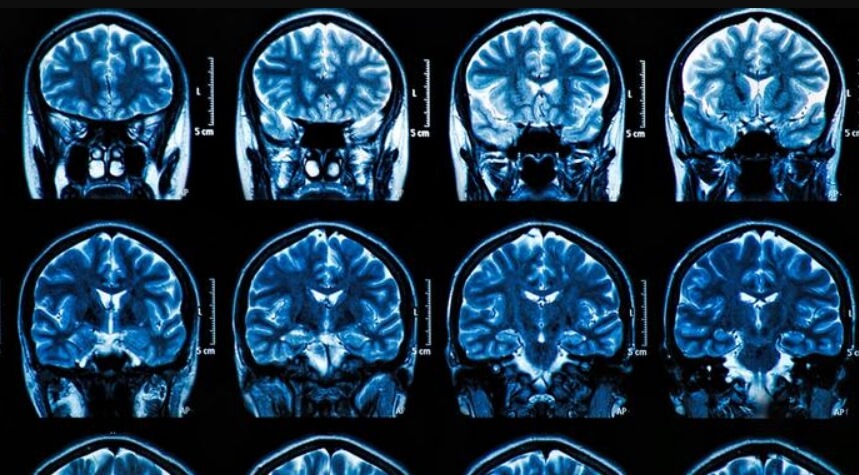

SARS-CoV-2 поражает разные органы человека, в том числе мозг

Хотя пока еще мало что известно о механизмах, лежащих в основе многих из этих симптомов, исследователи все больше полагают, что воспаление может играть ключевую роль. При коронавирусе возникает неконтролируемый иммунный ответ, который способен необратимо повредить или разрушить клетки мозга. А с повреждением мозга, судя по всему, меняется и личность человека.

Изменения в мозге, вызванные вирусом

Коронавирус разрушает нейроны в разных отделах мозга

Маура Болдрини, нейробиолог и психиатр из Колумбийского университета Манхэттена, была одним из первых, кто исследовал мозг людей и животных, умерших от COVID-19. Под микроскопом Болдрини и ее команда обнаружили изменения в гиппокампе, области мозга, которая находится глубоко в височной доле и играет важную роль в обучении и памяти. После перенесения болезни новых нейронов в этой части мозга было в десять раз меньше, чем должно быть.

“Мозговой туман приобрел для меня большой смысл, когда я увидела, что из-за COVID происходит потеря нейронов» — говорит Маура Болдрини.

Команда также обнаружила повреждение мозгового вещества, которое контролирует дыхание и движение. Другие исследователи обнаружили доказательства повреждения тканей более тонкой коры и потери серого вещества. Авторы отметили, что у госпитализированных пациентов наблюдалось значительно большее снижение когнитивных функций, чем у тех, кто перенес коронавирус в легкой форме.

Также ученые выяснили, что ключевые клетки в головном мозге, называемые астроцитами, подвержены прямому заражению вирусом. Кроме того, вирус может ухудшать приток крови к нейронам за счет сужения капилляров, то есть крошечных кровеносных сосудов. Это может объяснять, почему вирус часто вызывает инсульты.